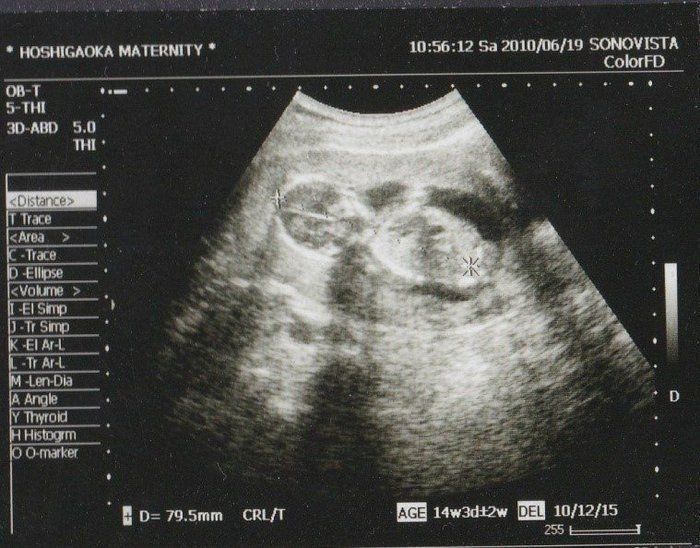

Amiさんの妊娠14週目のエコー写真

頭からお尻までの大きさが79.5mmにまで成長しました。左側に頭で右側が体です。腕らしいものも写っています。この週から待ちに待った経腹法でのエコー撮影でした。経膣法とは違い気分的にとても楽ちんでした。